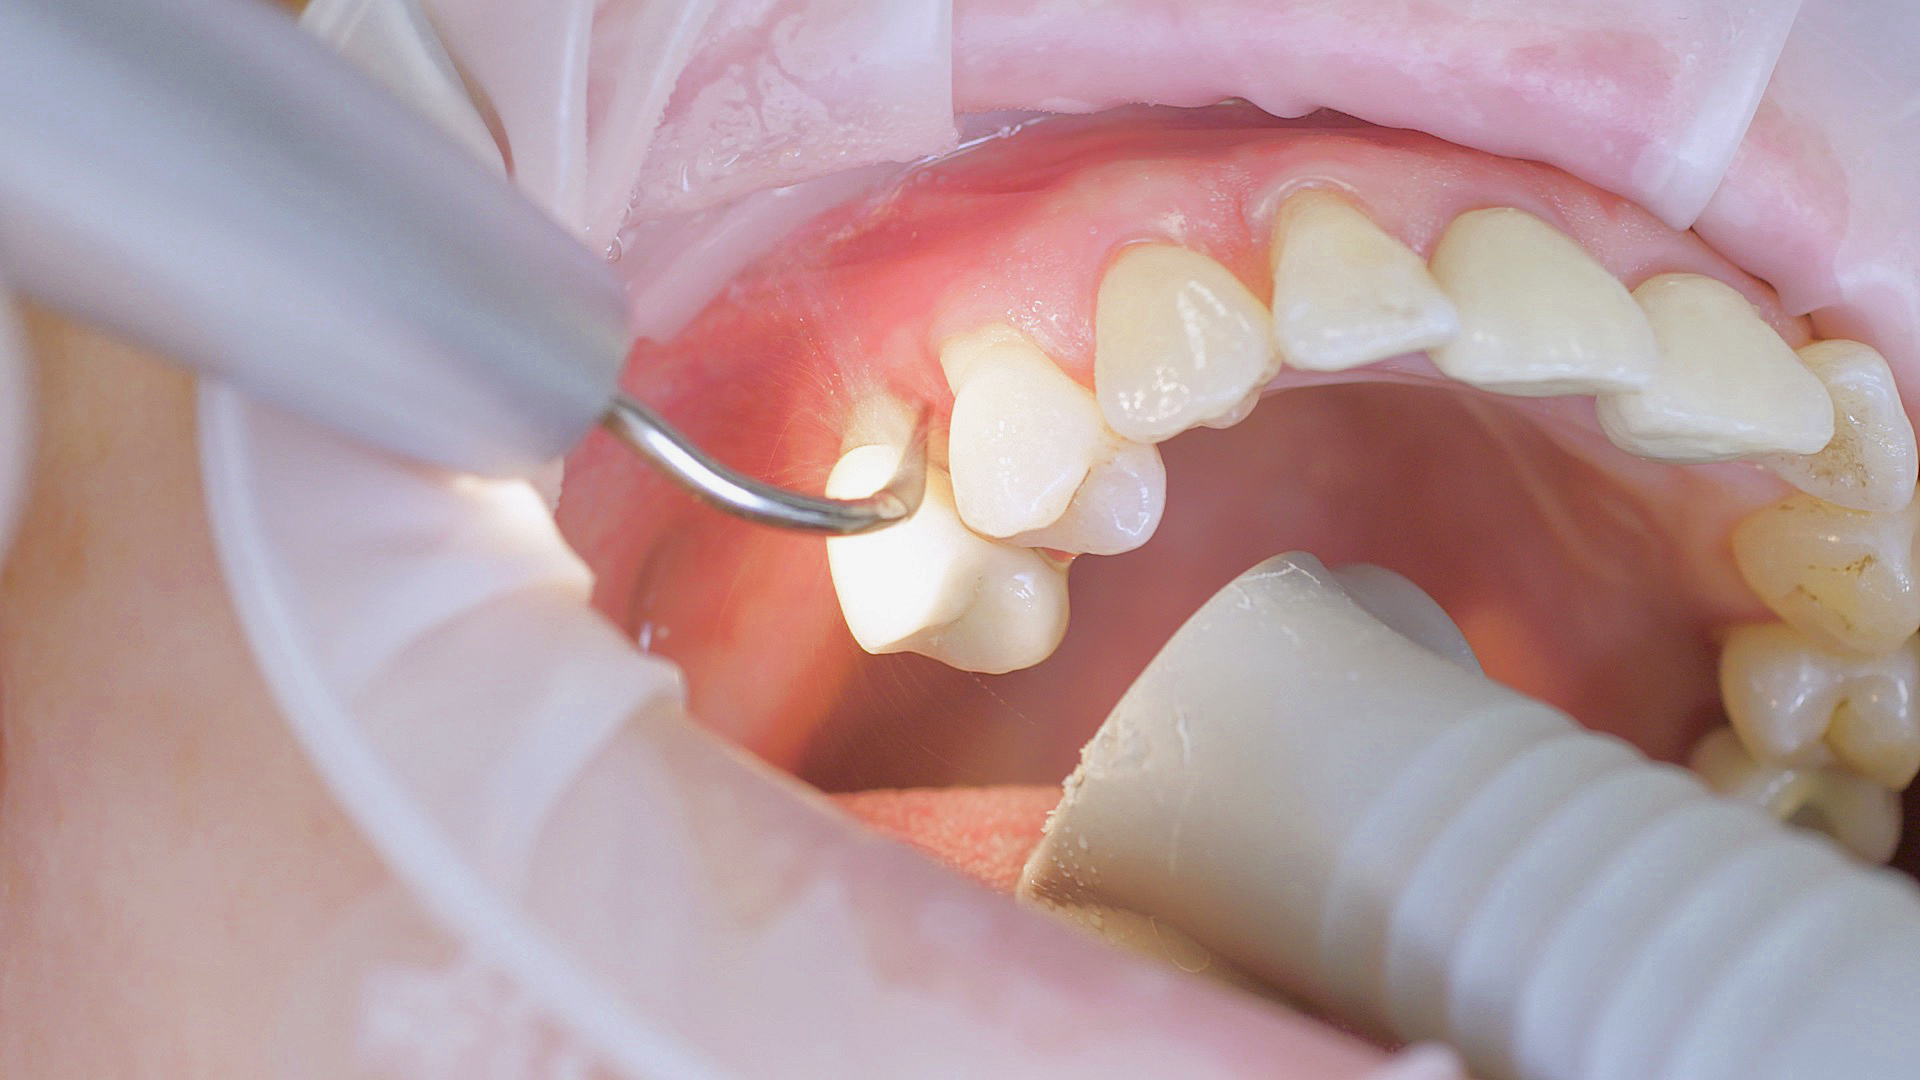

Tous les examens dentaires reposent sur l’étude des antécédents médicaux détaillés, associée à un diagnostic ciblé contenant le plus de détails possible. Le chirurgien-dentiste enregistre les facteurs de risque systémiques tels que le diabète ou le tabagisme et identifie toute augmentation de la tendance potentielle à l'inflammation.[3] Les tissus durs et mous sont examinés et les poches parodontales sont sondées dans le cadre d’un test de dépistage selon le PSR (Periodontal Screening and Recording). En cas de résultats anormaux, l’état du parodonte est ensuite enregistré et un traitement est démarré si nécessaire. Ce traitement débute par la gestion professionnelle du biofilm à l'aide par exemple de cupules rotatives et de composés de polissage (Fig. 1) et comporte des instructions complètes sur l’hygiène buccodentaire. Les systèmes à ultrasons restent une alternative ou un complément efficace aux instruments manuels pour le détartrage subgingival et la gestion du biofilm (présentation du Pr Dr Ulrich Schlagenhauf ;

Fig. 2). Le recours en complément à la thérapie photodynamique, à l’aéropolissage ou aux antibiotiques locaux et systémiques n’est pas suffisamment documenté (Pr Dr Sema Hakki).[4] D’après le Dr Sergio Bizzarro, un diagnostic amélioré des biomarqueurs peut conduire à une utilisation plus fréquente des thérapies personnalisées à l’avenir.

Un détartreur à air réalise un détartrage initial efficace, une étape du traitement parodontal initial.

Fig. 2 : Un détartreur à air réalise un détartrage initial efficace, une étape du traitement parodontal initial.